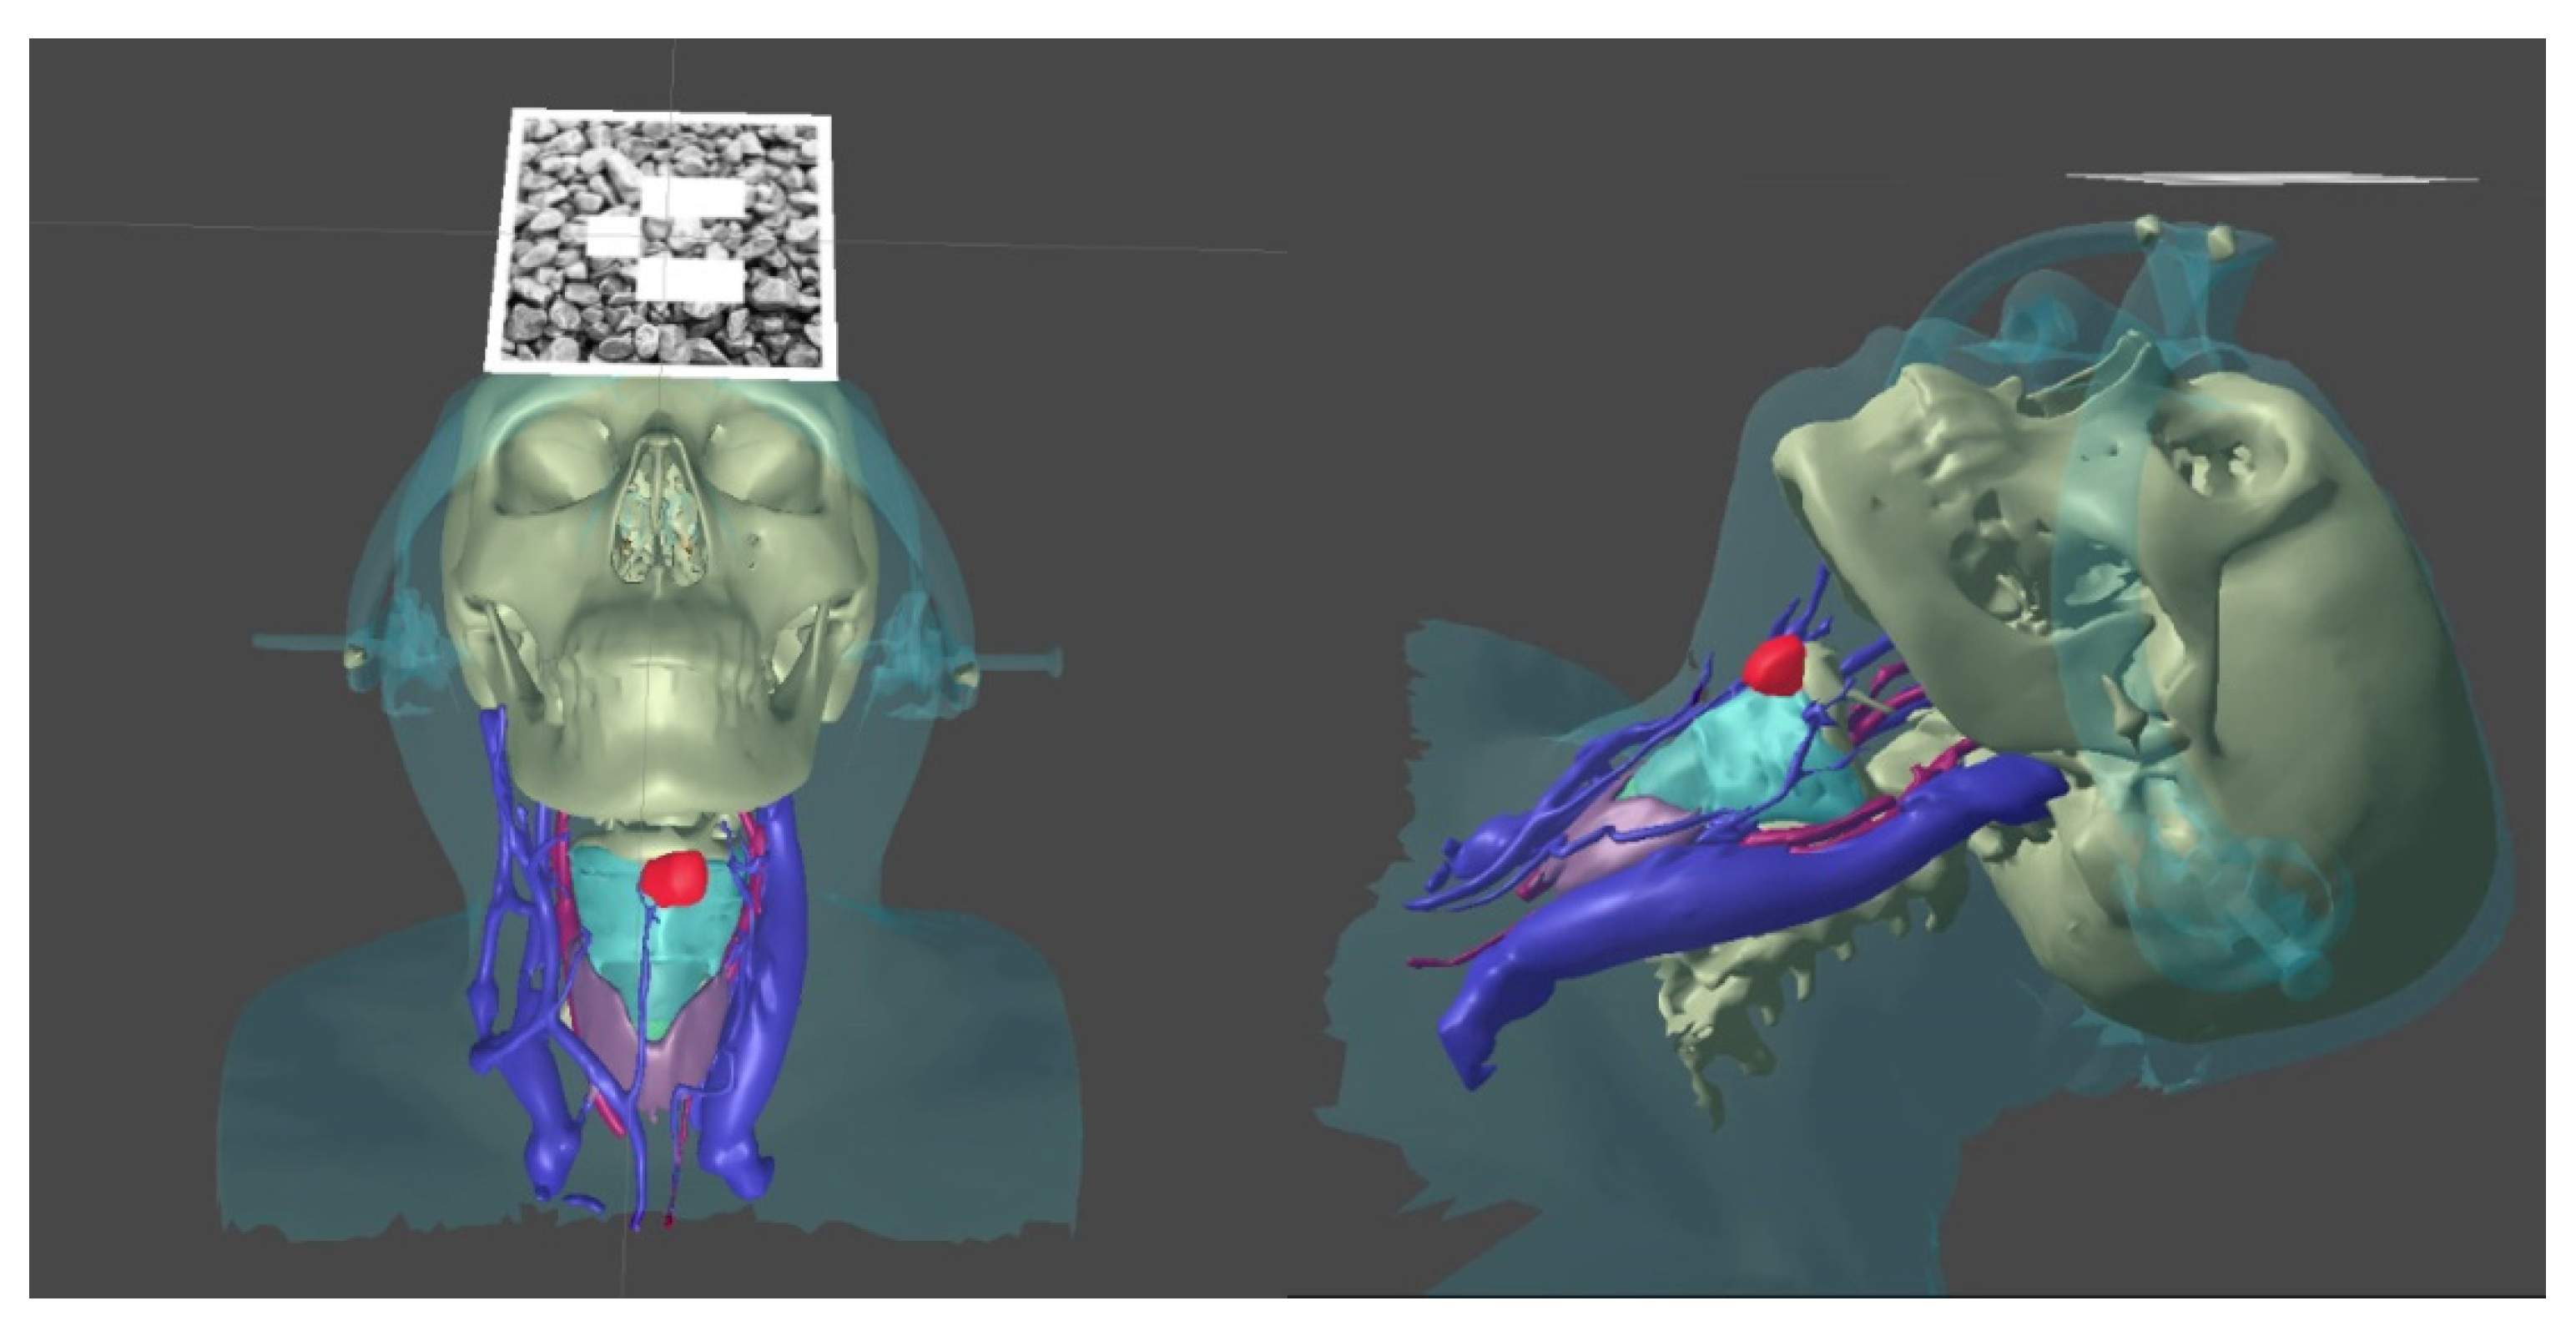

- We transformed the CT into a 3D model using a segmentation approach with respect to the set density threshold or the area of interest in the 3D Slicer. This allowed us to isolate all key anatomical structures of the neck as a series of separate three-dimensional models. After that, resulting 3D models were optimized and cleaned up using the procedural toolkit in Houdini (up to 75–95% polygon reduction); we then transformed the MSCT into a 3D model using a segmentation approach with respect to the set density threshold or the area of interest. This allowed us to isolate all key anatomical structures of the neck separately as a series of three-dimensional models;

- We visualized 3D models using mixed reality smartglasses and the developed software, which has preset parameters for referencing the markers to the three-dimensional model. It has an integrated basic interface [20], which allows the user to display the required anatomical elements as well as customize the parameters of the marker tracking system;

3.2. Case 2. Adjustable Navigation Frame

Operating Principle and Conclusion

3.3. Case 3. Adjustable Navigation Frame